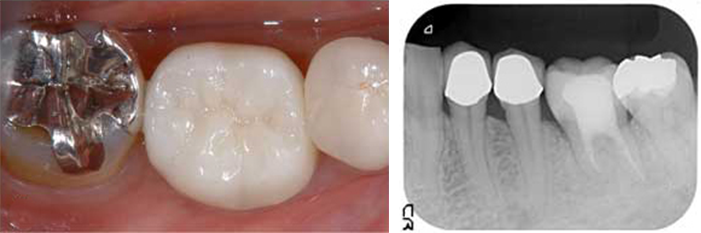

過去に抜いてインプラントにした方が良いと言われ 心配で当院を受診された35歳男性

BEFORE

向かって左端で横を向いてはえているのが親知らずを、抜歯せざるを得ない状態の放置された虫歯に移植します。

AFTER

治療後5年のレントゲンとそのカラー写真です。 この方の反対側の顎の中に埋もれている親知らずを抜歯し、即時移植で治療することができました。